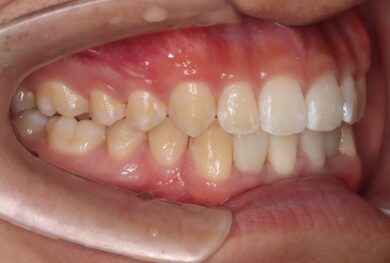

• 治療前

下顎の前歯は通常6本ですが、中央から2番目の歯(側切歯)が左右2本とも欠損している先天性欠如の患者様です。

初診時、下顎だけでなく、上顎の正中(真ん中)にも空隙(隙間)がありました。